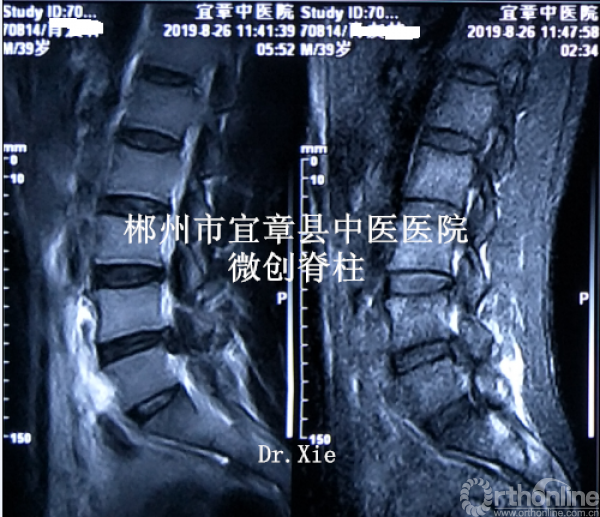

MRI、CT影像学表现:

既往体健。专科情况:L4/5稍有压痛,左臀部致左下肢伴有明显放射胀痛感,以左小腿前外侧为明显;左侧直腿抬高试验(+),左侧踇背伸肌肌力IV级,左下肢伴有明显跛行,左侧膝反射减弱,余(-)。

病程:腰痛伴左下肢放射痛5年,加重5天入院,入院诊断:L4/5椎间盘脱出伴坐骨神经痛。